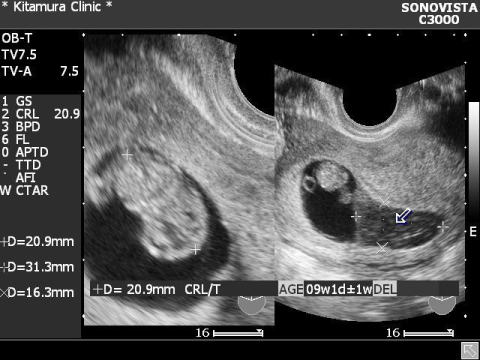

切迫流産(絨毛膜下血腫)

各超音波写真の上にマウスを移動してください。

写真上に説明が出ます。